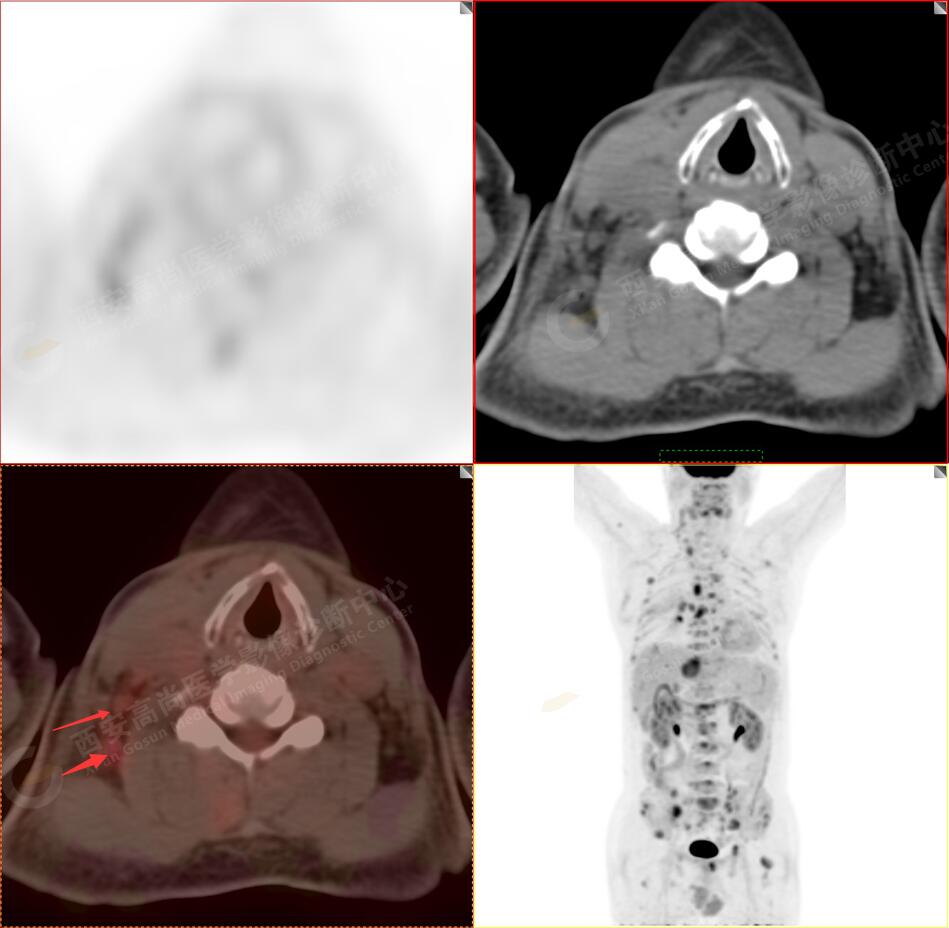

病史:男性,61歲,咳嗽1月余,CT發(fā)現(xiàn)肺結節(jié)。外院腋窩淋巴結穿刺活檢提示:轉移性腺癌。行PET/CT進行腫瘤分期。

3.右側頸部(Ⅱ-Ⅴ區(qū))、右側腋窩區(qū)、右側肺門及縱隔(1R、1L、2、4、6、7組)、肝門區(qū)多發(fā)腫大淋巴結,呈不同程度異常增高,均考慮為淋巴結轉移。